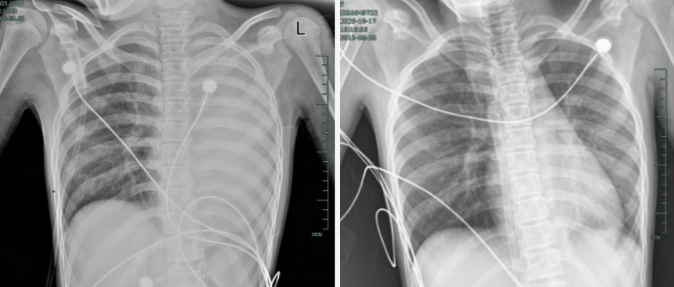

治疗前后影响对比,左肺从“白肺”到正常状态

呼吸急促、胸闷胸痛,体温38.5℃,只能靠 5L/min 的面罩吸氧维持血氧,胸片显示左肺已完全呈 “白肺” 改变,肺部炎症进展迅猛。